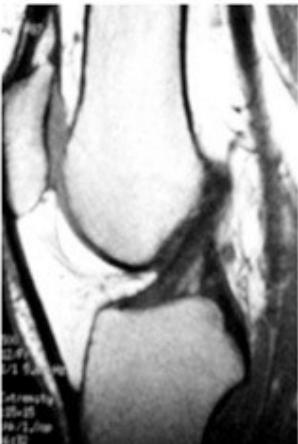

MRI (Gold Standard)

- Best imaging modality for ACL injuries

MRI Findings:

- Normal ACL